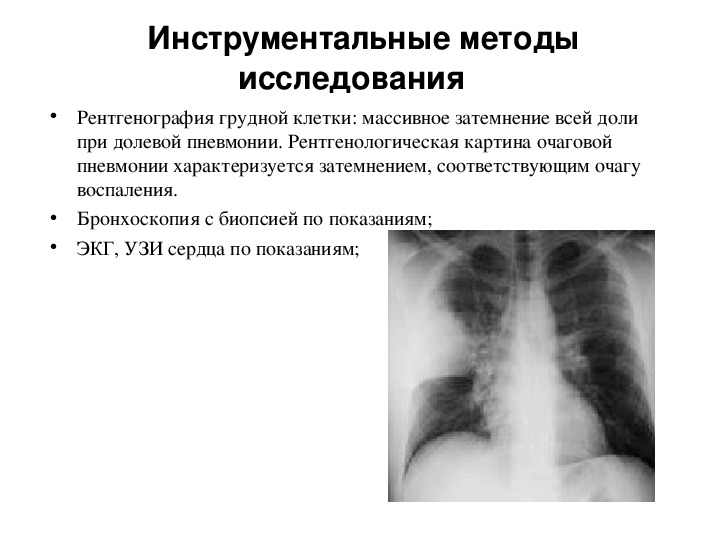

Фотографии и информация о бронхоскопии при туберкулезе